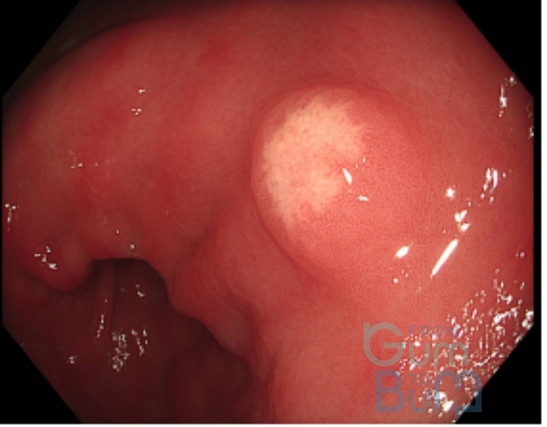

16 yo male attended with worsening RIF pain and guarding.  He reports having asthenia and weight loss over the last month.  He has not had diarrhoea.  His CRP is 110mg/l,  Hb is 10.2mgdl and white cells are 13000.

In view of suspicion of inflammatory process, a CT scan is done after a negative abdomen US for appendicitis.  CT confirms terminal ileitis confined to about 4cm of distal ileum.   Colonoscopy is performed with the attached image in the ileum, being the rest of the colonic mucosa and perianal area normal.

crohns TI